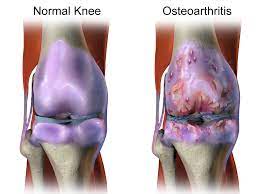

관절염 증상

- 통증: 관절 염증으로 인해 생기는 가장 대표적인 증상입니다. 활동하면서 또는 휴식할 때도 통증이 있을 수 있어요.

- 관절 부어오름: 관절이 부어오르거나 따뜻해지는 증상이 있을 수 있어요.

- 관절 강직: 오랫동안 움직이지 않거나 아침에 일어날 때 관절이 뻣뻣하게 느껴지는 것을 말해요.

- 팽만 및 충혈: 관절 주위의 피부가 붉어지거나 붓는 증상이 있을 수 있어요.

- 움직임 제한: 관절 통증 및 염증으로 인해 움직임이 제한되거나 유연성이 떨어질 수 있어요.

- 딸림 현상: 관절에 뼈가 부딪히거나 문제가 생기면 소리가 나거나 불안한 느낌이 들 수 있어요.